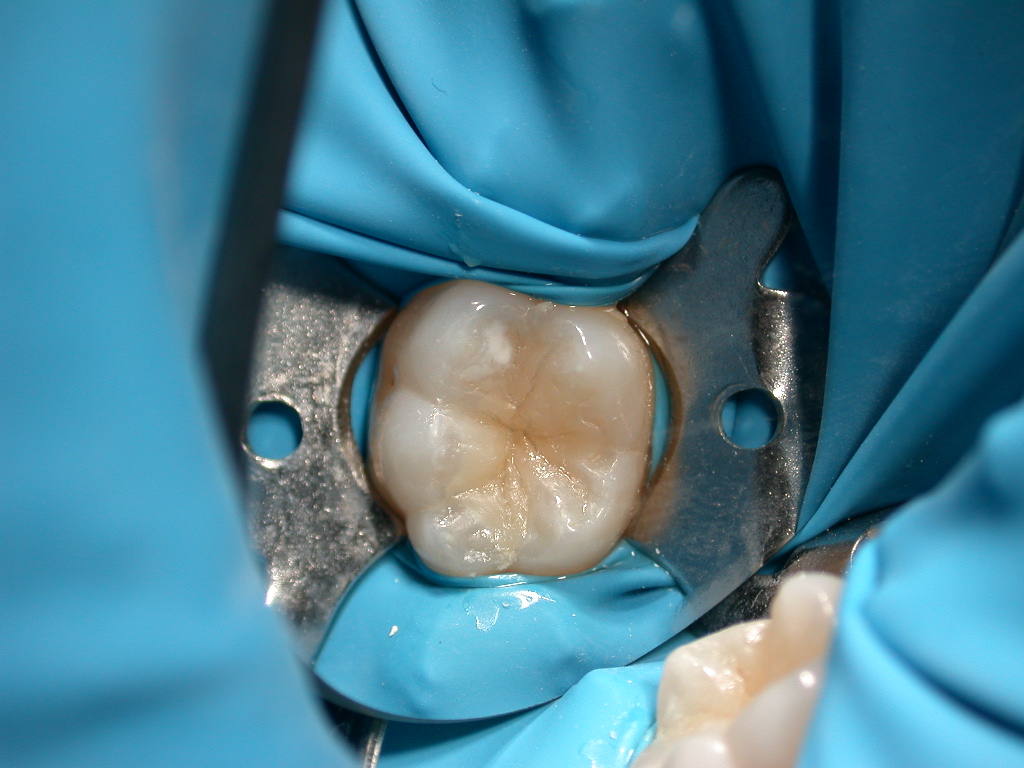

Eliminazione della carie e ricostruzione molare inferiore

restauro completato